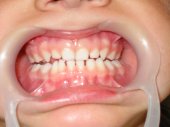

A la izquierda una mordida cruzada unilateral

tratada con efectividad con un tallado selectivo.

A la derecha un problema de masticación ineficaz por el lado izquierdo solucionado también con un tallado selectivo. |